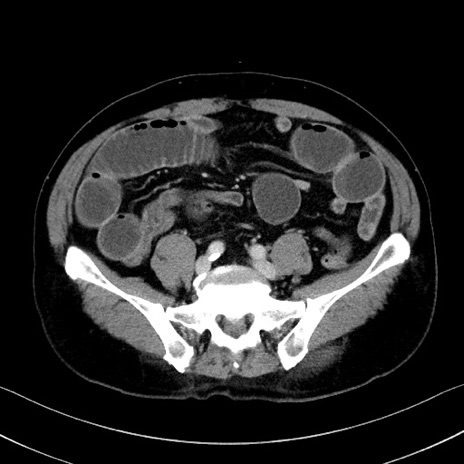

冠状断像

症例35(横断像)

【症例】70歳代 男性

【主訴】腹部膨満、嘔吐

【現病歴】昨日より腹部膨満感出現。本日増悪し、仙痛出現。嘔吐あり、受診。

【既往歴】糖尿病、胆摘後

【身体所見】BP 149/80mmHg、HR 74/min、BT 35.9℃、腹部:膨満、軟、圧痛なし。腸雑音減弱あり。上腹部正中切開瘢痕あり。

【データ】WBC 13500、CRP 1.72